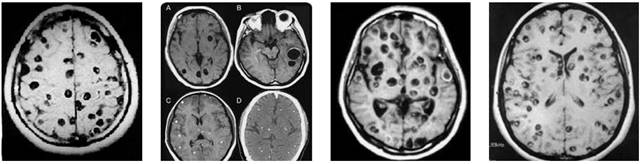

Hình 1

Hình 2

Hình 3

Hình 4